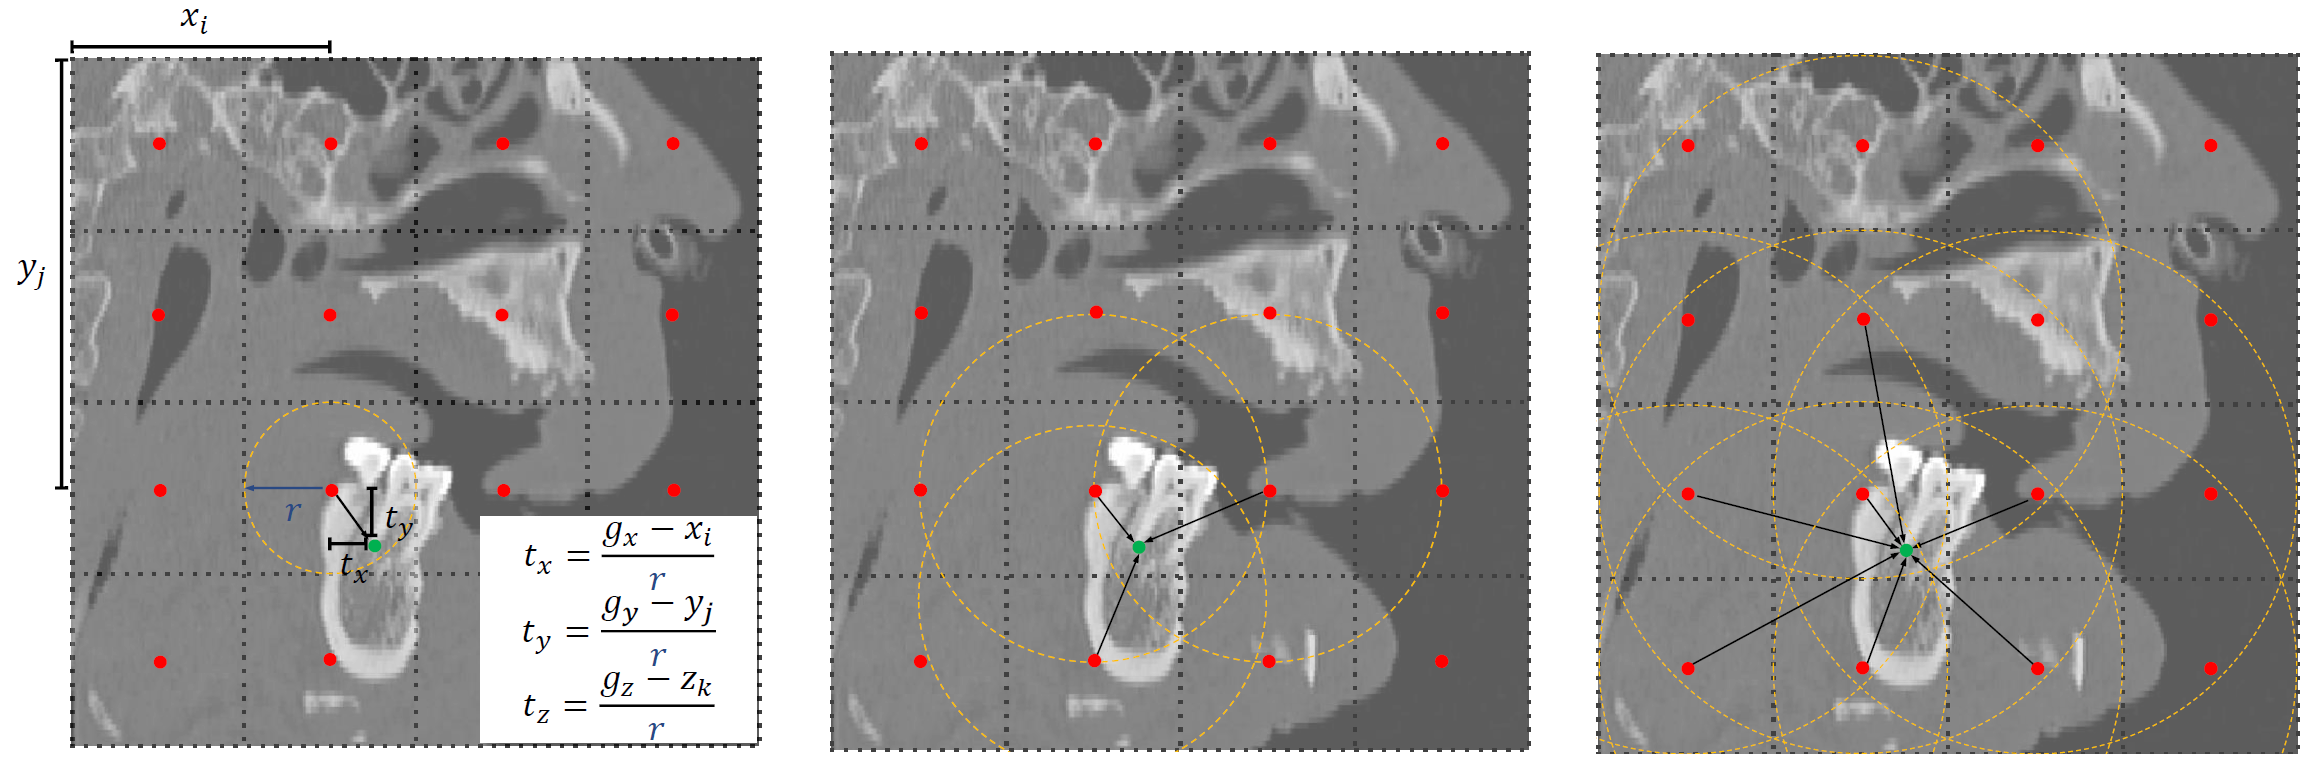

- We compared baseline deep learning methods in three aspects: landmark regression models, training losses, neural network structures. An ABR model inspired by YOLOV3 surpassed other baselines. The model combines landmark regression and classification losses for network training, resulting in better performance than the usual heatmap and offset regression methods.